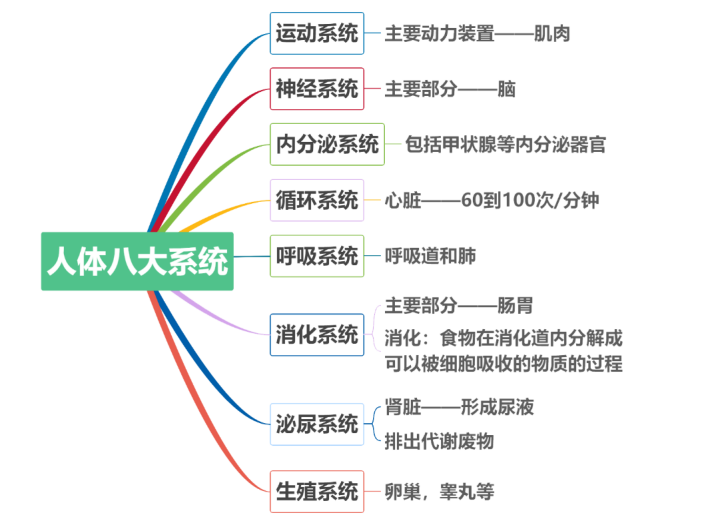

干細胞被稱為生命的種子細胞,是一類具有自我復制更新和多向分化潛能的原始細胞。在運動、神經(jīng)、內(nèi)分泌、血液循環(huán)以及呼吸等八大系統(tǒng)中,干細胞發(fā)揮著極為關(guān)鍵的作用。